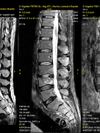

IRM Rachidienne

L’IRM rachidienne est un examen qui permet d’étudier l’ensemble du rachis et de la moelle épinière : rachis cervical, rachis dorsal, rachis lombaire.

L’IRM contribue à la détection des anomalies présentes au niveau des corps vertébraux et des disques.